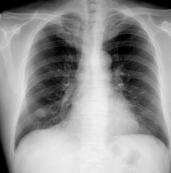

肺錯構瘤是指包含肺的所有正常組織成分, 但構成成分數量異常、排列異常或分化程度異常等所形成的腫瘤樣畸形。肺錯構瘤不是真性腫瘤(也有研究者主張其為真正的腫瘤),而是胚葉的發育異常,起源于肺內正常組織,主要為軟骨、纖維結締及脂肪組織等形成的腫瘤樣病變。因其性質及影像學特征近似良性腫瘤,故列為良性腫瘤范圍內。根據其成份分為軟骨型及纖維型。根據部位分中央型和周圍型 。發生于氣管、葉支氣管粘膜下稱中央型。發生于肺內的稱周圍型,周圍型多位于胸膜下。